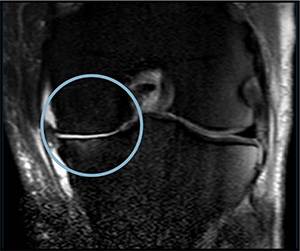

PRE-TREATMENT

NOVEMBER 2023

POST-TREATMENT

NOVEMBER 2024